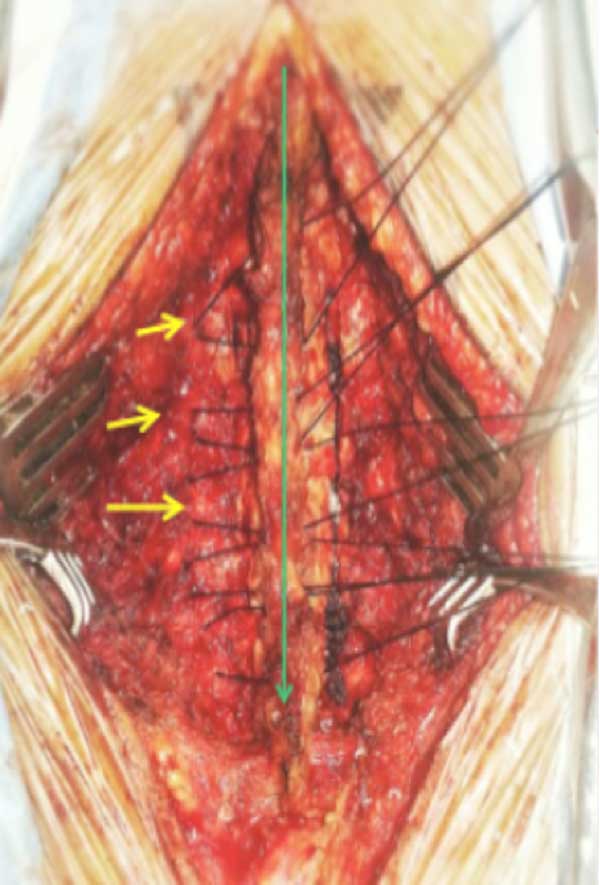

Se efectúa una osteotomía completa de aproximadamente 3 mm de diámetro (con fresa AM-8 y, de ser necesario, se puede completar con Kerrison de 2 a 3 mm) en el punto de unión laminoarticular del lado izquierdo y la osteotomía incompleta, de mayor tamaño, respetando la cortical anterior en el mismo sitio contralateral (solo se elimina una capa cortical y hueso esponjoso). La dirección de los cortes debe tener una angulación levemente medial para evitar lesionar el macizo articular (Figuras 3 y 4). Se escinde el ligamento amarillo en el espacio intermedio C2-C3 y el espacio intermedio C7-T1 con Kerrison de 2 mm, también las adhesiones durales en el lado de apertura.

Figura 3. Imagen intraquirúrgica donde se observa la disección de los planos musculares hasta el borde externo articular y posterior colocación de puntos espinoarticulares (flechas amarillas) utilizados como puntos de anclaje.